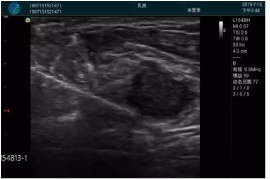

清晰顯示腺體內(nèi)低回聲快影,邊界清晰,包膜較光滑

確定進(jìn)針路徑并實(shí)時(shí)監(jiān)測抽吸針與腫塊位置關(guān)系

抽吸針進(jìn)入腫塊內(nèi)部進(jìn)行旋切

抽吸過程中可見腫塊明顯縮小,并根據(jù)腫塊位置改變針道位置

抽吸旋切后再進(jìn)行超聲復(fù)查,原腫塊區(qū)域未見殘留組織及出血